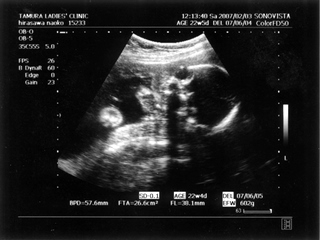

5ヶ月(18週と5日) 体重:262g BPD(頭を上から見た耳から耳の幅のような感じ):46.8㎜ FTA(お腹の断面):15.9平方㎝ FL(大腿骨長 太ももの骨の長さ):22.7㎜ 6ヶ月(22週と5日) 体重:602g BPD(児頭大横径 頭を上から見た耳から耳の幅のような感じ):57.6㎜ FTA(体幹横断面 お腹の断面):26.6平方㎝ FL(大腿骨長 太ももの骨の長さ):38.1㎜ まだこの頃は顔と上半身が収まっていました。 検診は妊娠23週までは、4週に一度なのでドキドキとワクワクです。 ちゃんと成長してるかなあなんて考えて行って、 心音をきいたり、エコーを見て毎回安心と喜びがわいてきます(*^_^*) たった4週で、体重は3倍近くにも!かわいいなあ☆ 6ヶ月の検診日ダンナっちは仕事だったから、 エコー写真を携帯で撮って送ると、 『目ん玉でてない!?』 と返事が返ってきました。 眼球がそう見えるんだろうけど、目のとても細いダンナっちには 衝撃的だったんですね(^。^;) 胎動を初めて感じた日をわたしはわかりません・・・ メモにとるなり、日記にかくなりすることをすっかり忘れてしまって、 今となって後悔<<o(>_<)o>> ダメな母親めっ と思いつつも、わたしらしいと感じ笑っています(^_^;) 12月の末に友達に、 「腸の動きか!?って思うのはあるんだけどまだよくわかんない」 と言ったのを覚えているので、12月の終わりから1月にかけての あたりなんでしょうね。 いつの間にかポッコポッコしていました! ベイビーこんなママだけどよろしく└|∵|┐♪┌|∵|┘ 6ヶ月までは、普通にそれまで履いていたジーンズも入っていたんだけど、 6ヶ月終わるころには、急に入らなくなってビックリしました~ 食生活の変化も特になかったです。 あ、ポテトチップスあまり自分で 買わなかったのに、1週間くらいブームの時期がありました!妊娠による影響かな!? 今、ベイビーはしゃっくりをしているみたいです |